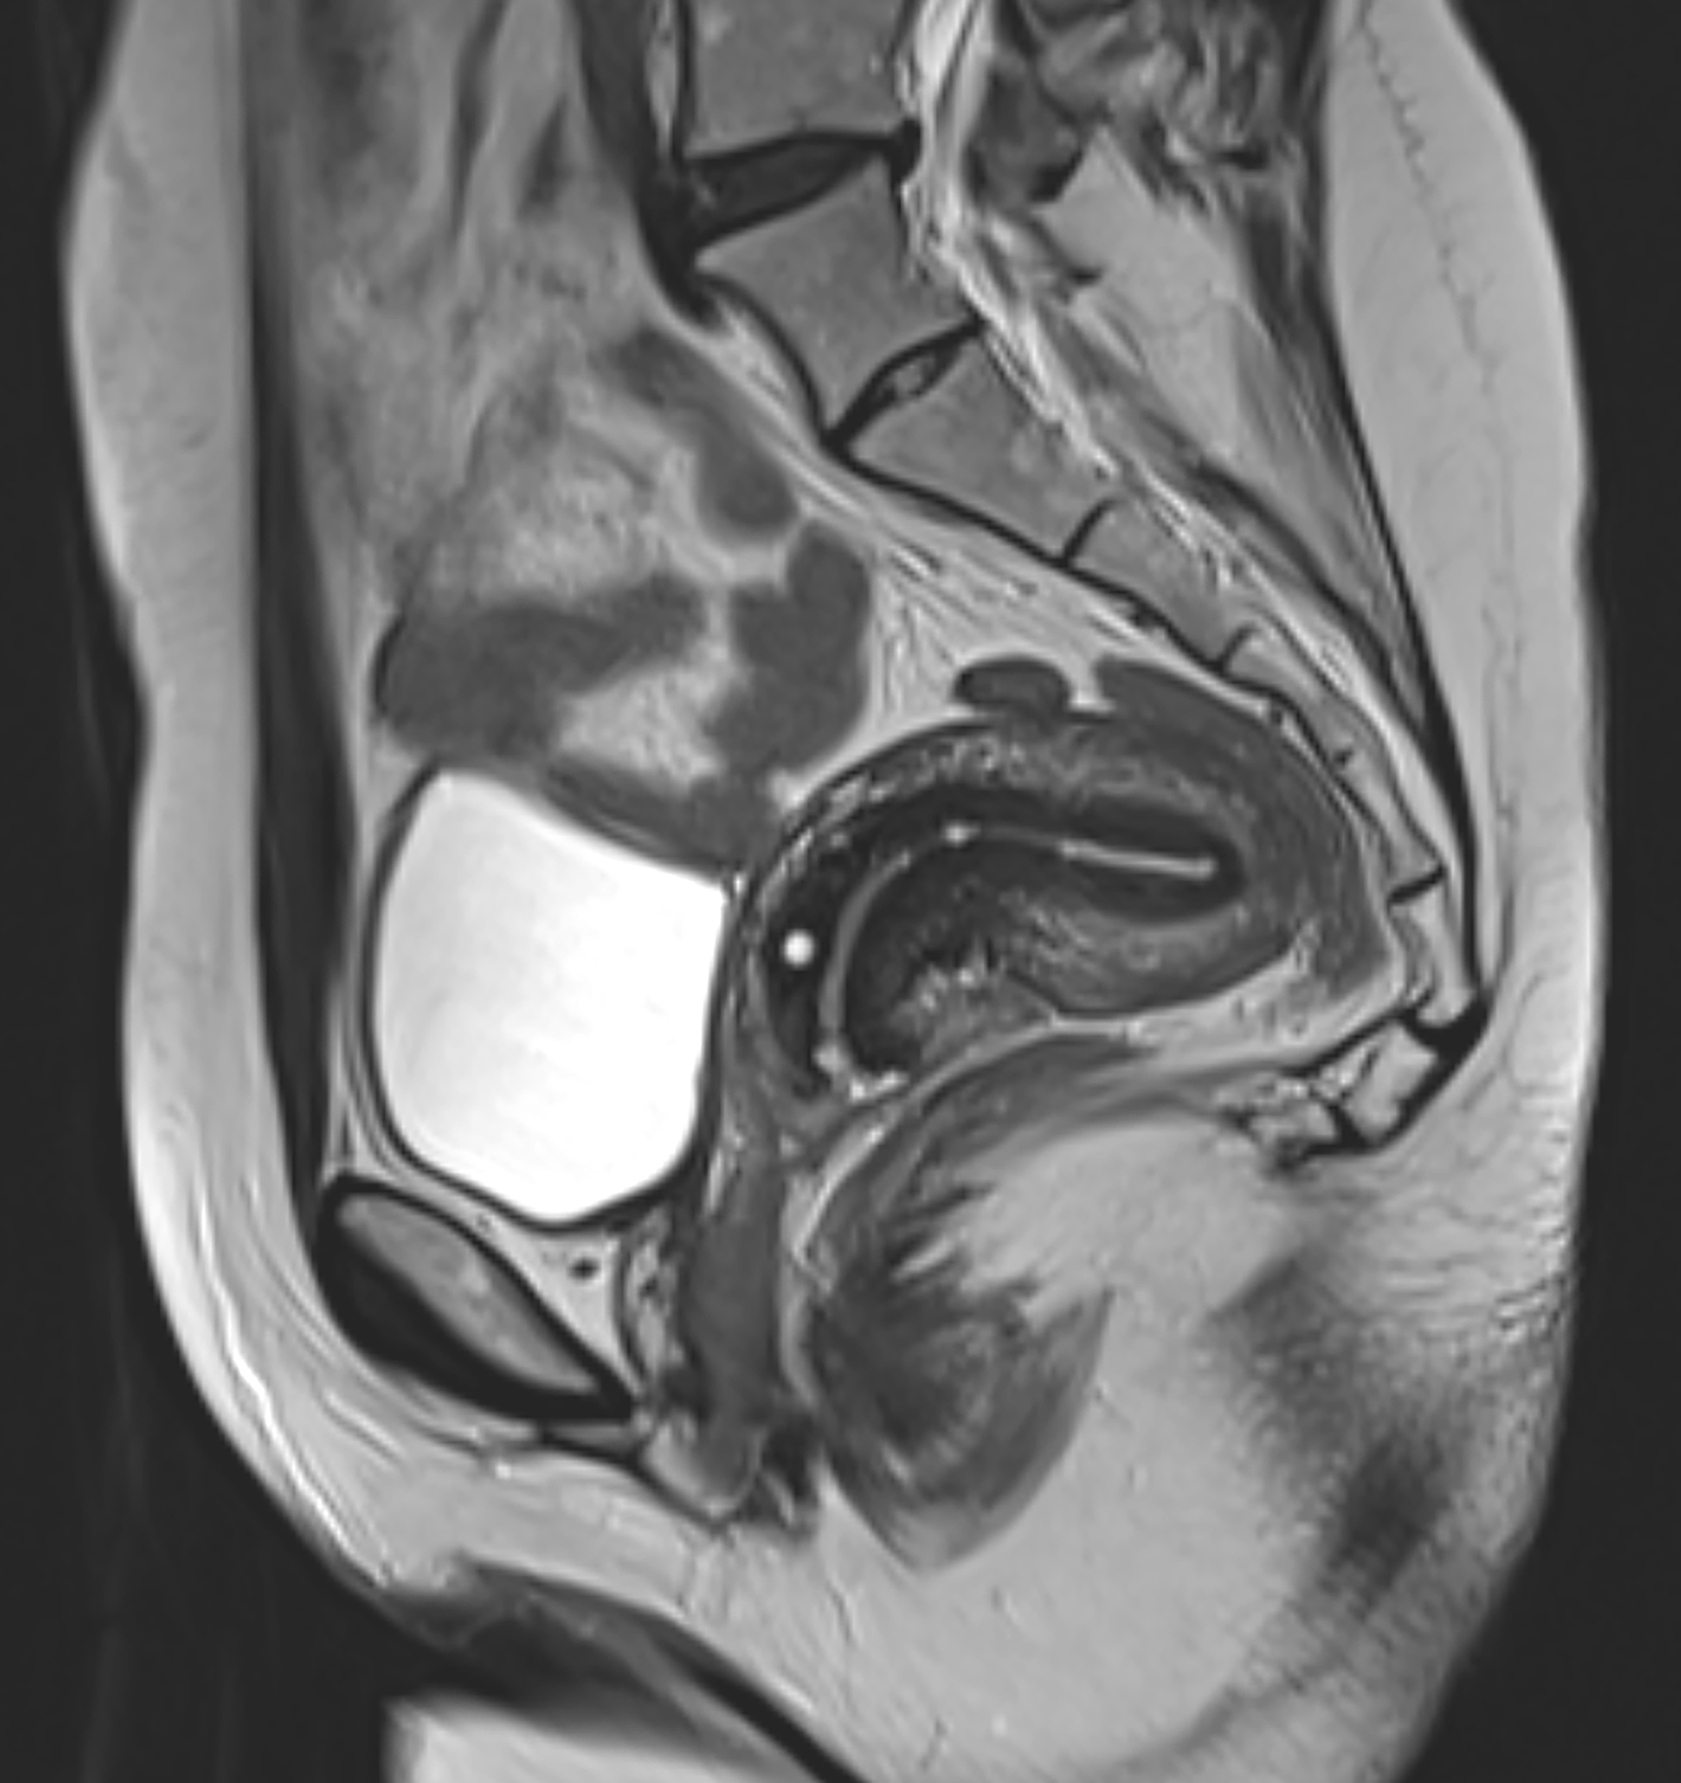

14.“I learned while I was pregnant with my oldest that I have a retroverted uterus, meaning my uterus is facing backward. It’s not super rare —it occurs in roughly 20% of women— but it certainly helped because I didn’t show until I was five months along with all three of my kids. Back labor is way worse, but the visible recovery was great… I was able to wear normal clothes almost immediately since everything was leaning back into my body.”